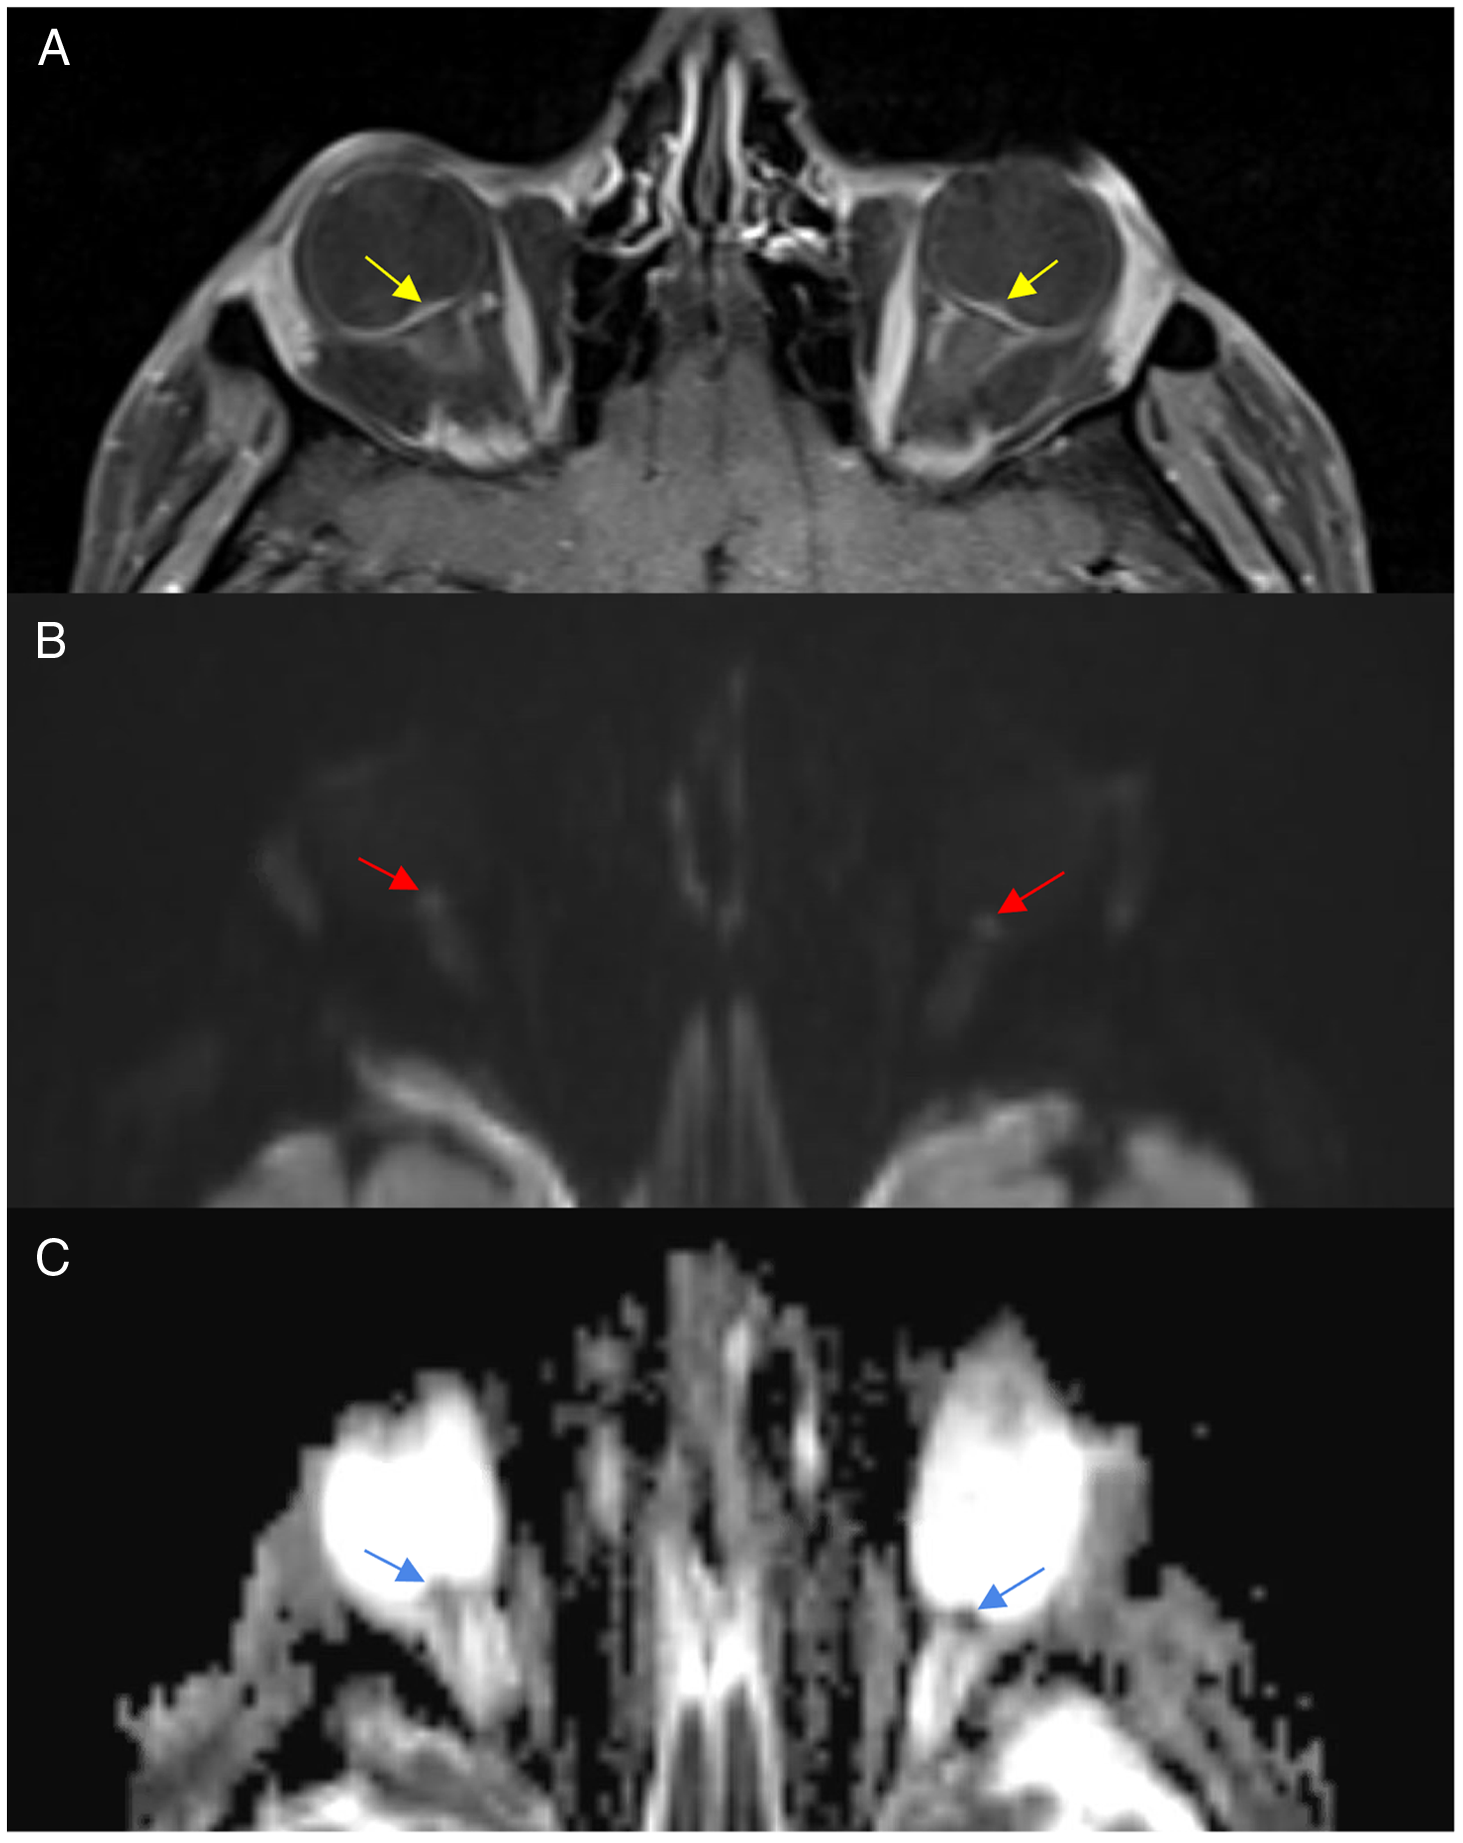

Figure 2: Magnetic resonance imaging T1-post-contrast with fat suppression (A), diffusion-weighted imaging (B) and apparent diffusion coefficient demonstrating flattening of the posterior sclera and optic nerve head enhancement (A), increase signal on DWI (B) and low signal on ADC (C).

This patient’s visual function continued to gradually decline in both eyes despite increased topiramate dosing, the addition of methazolamide, and dexamethasone. Three months after initial presentation, his visual acuity declined to no light perception OD and 20/500 OS. He had interval atrophy of his optic nerves and increasing hemorrhages in the retina. He underwent a repeat MRI orbits and brain that showed severe flattening of the posterior sclera and enhancement of the optic nerve head. On DWI sequences, there was restricted diffusion within the head of the optic nerve with associated low ADC signal. His vision declined to no light perception in both eyes 2 weeks later and he died 6 months later.